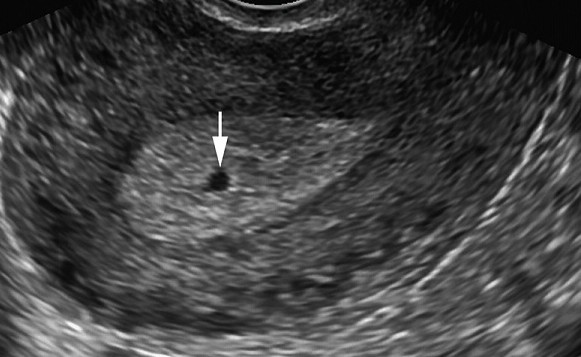

Bos Gebelik Nasil Anlasilir Belirtileri Nelerdir Gebe Com

Bos Gebelik Belirtileri Neden Olur Kacinci Haftada Belli Olur Goruntuleri

Bos Kese Gebelik Nedir Nedenleri Nelerdir Bebek Com